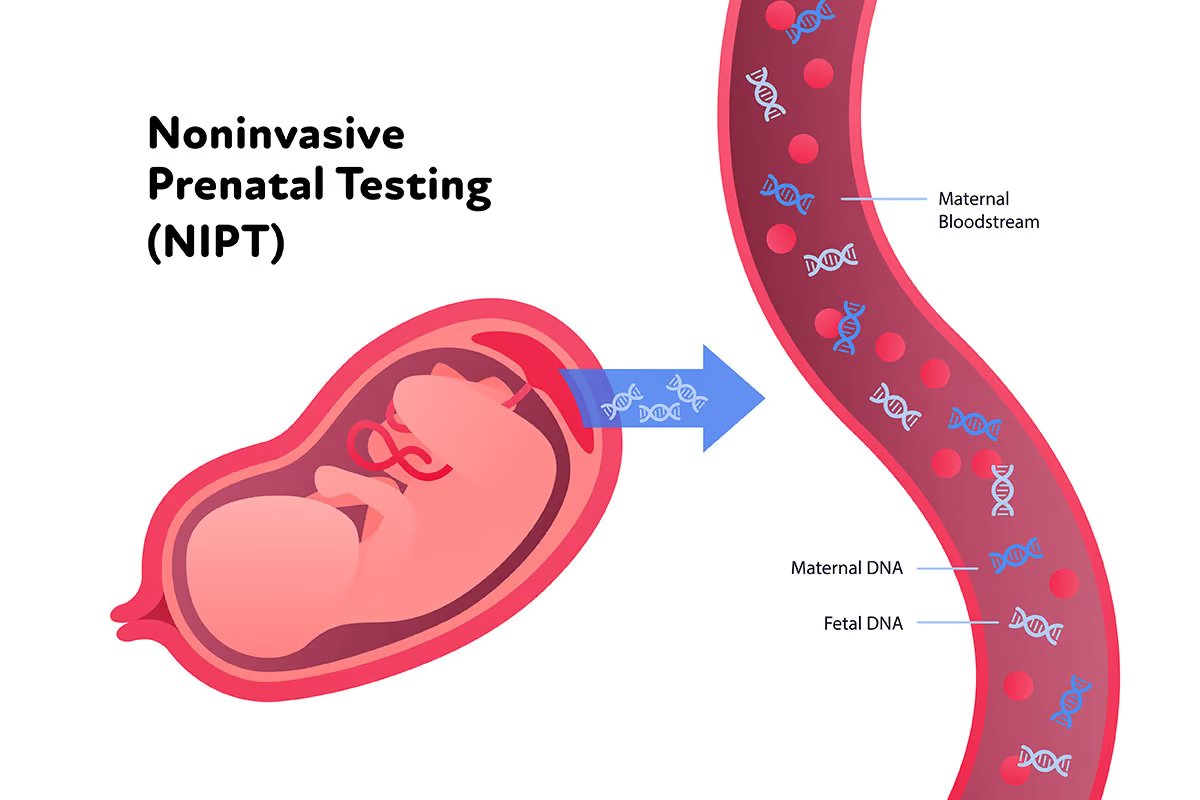

Advanced genetic testing and molecular diagnostics.